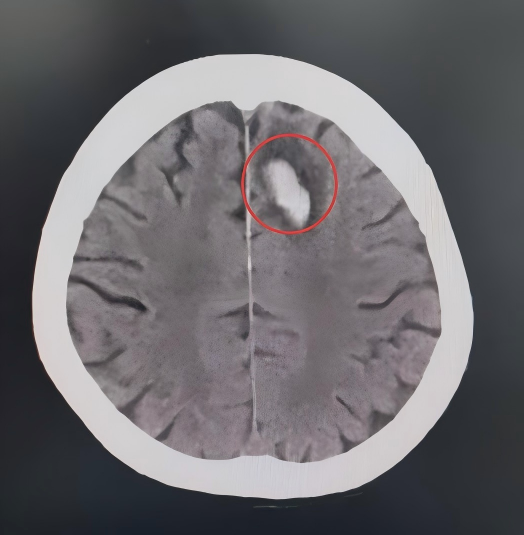

急诊团队迅速完成张大爷的心率、血压、血氧饱和度等关键指标监测。综合检查提示:老人左侧额叶脑挫裂伤,左侧股骨颈骨折,全身多处擦伤。

白色为创伤性颅内血肿,周边黑色为水肿

可以明显看到血肿和水肿范围在不断扩大

病情随时可能出现变化

张大爷的骨折和坏死需要尽快行手术恢复,但脑部的挫裂伤脑将在伤后48-72小时达到水肿高峰期,此时行手术,麻醉风险极高。另外考虑到张大爷的高血压已达到2级,过高的血压会加重颅内出血和脑水肿,过低的血压则可能会再次诱发脑梗。